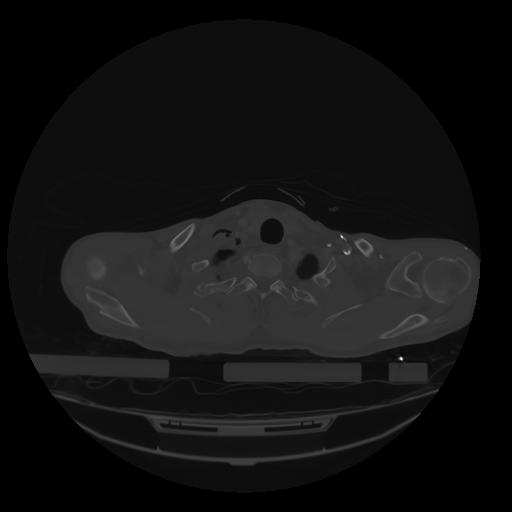

28 CUERPO,CE,Vol,2.0,CUERPO,,